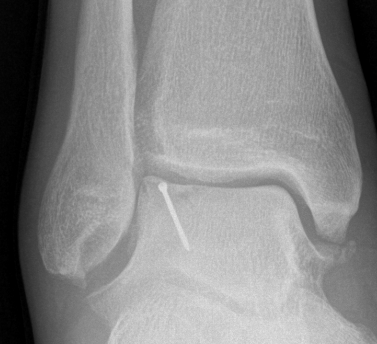

Xray

Stage II medial osteochondral fragments

Stage III medial osteochondral fragments

Stage IV anterolateral osteochondral fragment